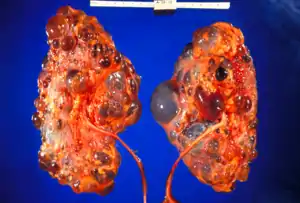

Renal pathology

Renal pathology is a subspecialty of anatomic pathology that deals with the diagnosis and characterization of disease of the kidneys. In a medical setting, renal pathologists work closely with nephrologists and transplant surgeons, who typically obtain diagnostic specimens via percutaneous renal biopsy. The renal pathologist must synthesize findings from traditional microscope histology, electron microscopy, and immunofluorescence to obtain a definitive diagnosis. Medical renal diseases may affect the glomerulus, the tubules and interstitium, the vessels, or a combination of these compartments.